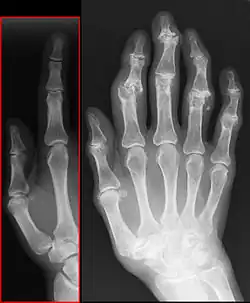

- Bouchard-Arthrose – Arthrose der Fingermittelgelenke

- Heberden-Arthrose – Arthrose der Fingerendgelenke